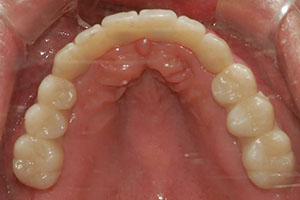

치료증례 전후사진

Before & After